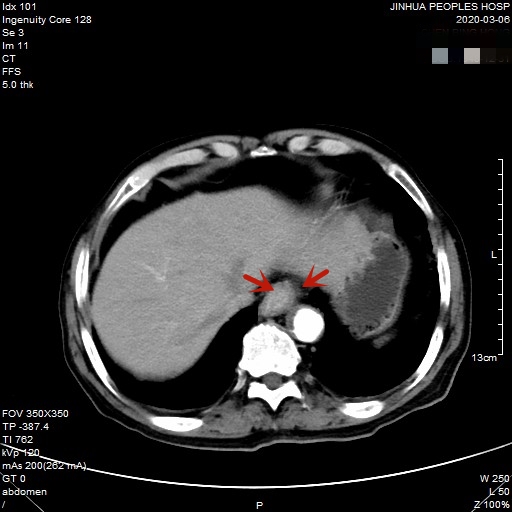

医生予以进一步检查CT增强发现肿瘤倒是没有明显侵犯周围脏器或结构,请我去会诊后,仔细阅片,发现从影像上看还是能够根治性切除的。所以转来胸外科拟进一步行手术治疗。下面是其CT增强的图像:

以上图片红色箭头所指处为贲门部肿瘤